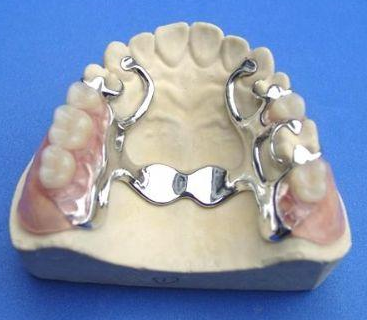

3、义齿:义齿有活动义齿和固定义齿。活动义齿会比固定义齿少磨牙,但是在清洁和护理的时候,活动义齿会来回摘戴比固定义齿繁琐一些。而且活动义齿的口感也会比较差一些。》》》推荐阅读:什么是种植牙?成功率是多少?有风险吗?